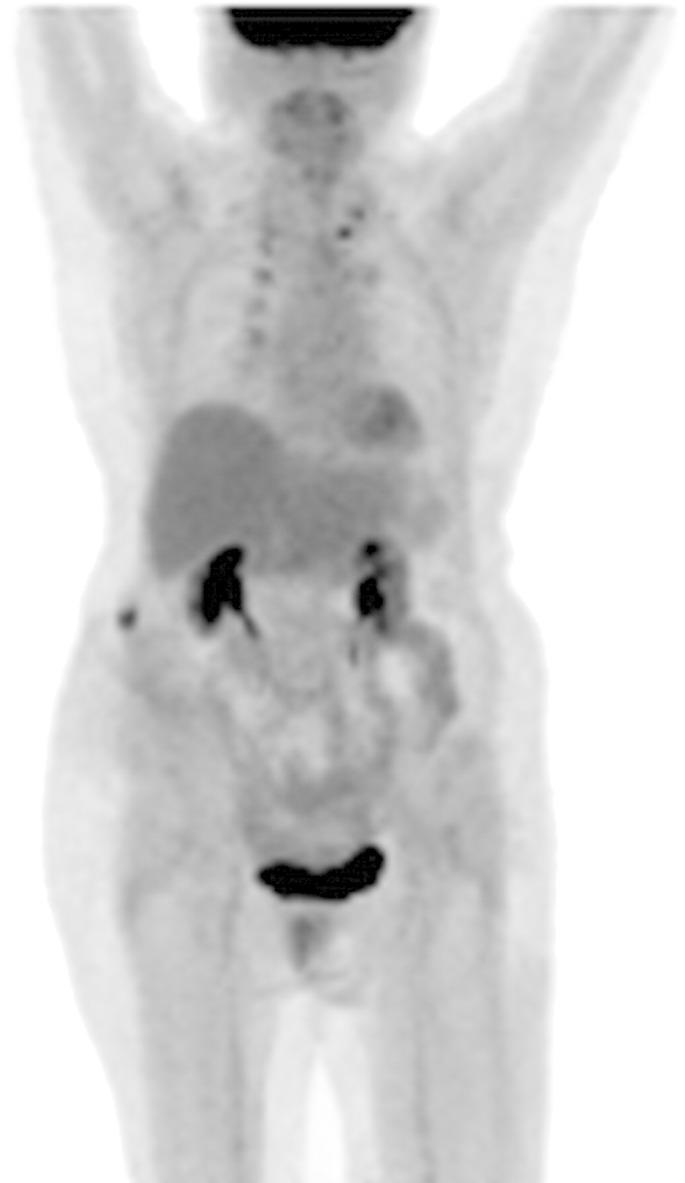

A 71-year-old woman with suspected endometrial cancer underwent robotic-assisted hysterectomy, bilateral salpingo-oophorectomy, pelvic and para-aortic lymph node dissection, and infracolic omentectomy revealing a stage II uterine carcinosarcoma with components of serous adenocarcinoma and undifferentiated spindle cell sarcoma. There was no evidence of distant metastasis at the time of surgery. However pelvic washings were positive for malignant cells. She received adjuvant chemotherapy and vaginal cuff brachytherapy. Forty months later she developed a subcutaneous mass at the location of previous port site which was confirmed to be recurrence of the uterine primary. She subsequently developed additional distant metastases to the abdominal wall, lungs, and bone. Port site metastasis (PSM) was the earliest indicator of disseminated metastatic disease in this patient. We review challenges in the management of patients with PSM and propose that PSM be considered as a sign of systemic disease even when presenting as an apparently isolated recurrence.

一名疑似子宫内膜癌的71岁女性接受了机器人辅助子宫切除术、双侧输卵管卵巢切除术、盆腔及腹主动脉旁淋巴结清扫术和结肠下网膜切除术,结果显示为II期子宫癌肉瘤,伴有浆液性腺癌和未分化梭形细胞肉瘤成分。手术时未发现远处转移的证据。然而,盆腔冲洗液中发现恶性细胞呈阳性。她接受了辅助化疗和阴道残端近距离放射治疗。40个月后,她在先前端口部位出现皮下肿块,经证实为子宫原发灶复发。随后,她又出现了腹壁、肺部和骨骼的远处转移。在该患者中,端口部位转移(PSM)是播散性转移性疾病的最早指标。我们回顾了PSM患者管理中的挑战,并提出即使PSM表现为明显孤立的复发,也应将其视为系统性疾病的迹象。